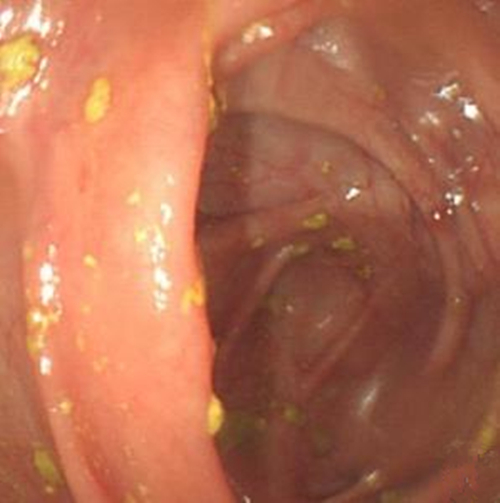

慢性結腸炎圖片

缺血慢性結腸炎患者

缺血性慢性結腸炎的

缺血性慢性結腸炎患者